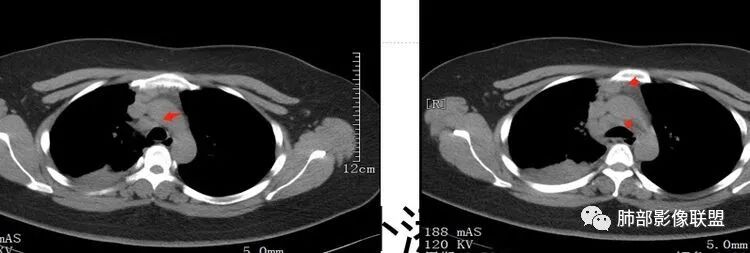

女,27岁,右肺下叶支气管闭塞,圆形软组织肿块和不张肺,增强不均匀强化,见片状坏死,多个纵隔淋巴结肿大,无钙化空洞及卫星灶;考虑恶性占位,肺肉瘤或鳞癌合并肺不张,鉴别诊断:结核,肺脓肿

右肺下叶支气管闭塞,圆形软组织肿块和不张肺,增强不均匀强化,见片状坏死,多个纵隔淋巴结肿大,无钙化空洞及卫星灶。鳞癌?肺脓肿?

发热咳嗽,右肺下叶可见团块状实变密度影,局部膨隆,并可见胸膜牵拉,相应下叶支气管未见显示,增强后肿块近端呈不均匀强化,可见大片状坏死,内血管略变细,毛糙,周围肺组织支气管内可见粘液栓形成,另纵膈肿大淋巴结,考虑恶性肿瘤,鳞癌,伴阻塞性肺不张,淋巴结转移

CT扫描示右肺下叶支气管堵塞,类圆形大肿块伴胸膜下大片肺实变影,增强扫描类圆形肿块延迟强化,见少量坏死,余实变区增强可见内部血管走行。纵隔见肿大淋巴结。考虑为恶性病变伴右肺下叶肺不张

右下肺门不规则结节强化,并远端支气管粘液栓及大片实变,实变边缘叶间裂膨隆,考虑支气管占位并阻塞性肺炎,涎腺类恶性肿瘤(粘液表)需要鉴别。

右中间支气管阻塞,右肺下叶实变,未见明显支气管空气征,增强中间支气管内病变未见明显强化,纵隔淋巴结增大,偏向恶性病变,结合病史,青年人,肿瘤性病变,支气管表皮样粘液癌可能。

患者青年女性,发热6 天,咳嗽、咳痰3天。为黄脓痰。胸部CT:右肺体积稍小,右中间支气管肿物堵塞,中叶、下叶大片实变不张,与正常肺组织分界清楚。增强实变影明显强化,右下肺支气管近心端见类圆形强化结节影,血管纤细,部分支气管显影变细,纵隔淋巴结肿大。结合无呼吸困难症状,病程长。综合考虑低度恶性病变并阻塞性肺炎,类癌可能大,鉴别结核、淋巴瘤。

右肺中下叶实变伴气管腔内粘液栓形成,肺门区见不规则软组织肿块,气管腔狭窄,截断,呈中等强化,纵膈内肿大淋巴结,考虑气管腔内原发肿瘤性病变伴肺实变